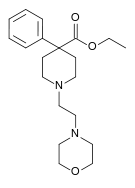

The first fully synthetic opioid was meperidine (later demerol), found serendipitously by German chemist Otto Eisleb (or Eislib) at IG Farben in 1932.[228] Meperidine was the first opiate to have a structure unrelated to morphine, but with opiate-like properties.[199] Its analgesic effects were discovered by Otto Schaumann in 1939.[228] Gustav Ehrhart and Max Bockmühl, also at IG Farben, built on the work of Eisleb and Schaumann. They developed "Hoechst 10820" (later methadone) around 1937.[230] In 1959 the Belgian physician Paul Janssen developed fentanyl, a synthetic drug with 30 to 50 times the potency of heroin.[211][231] Nearly 150 synthetic opioids are now known.[228]

Phenylpiperidines

- Pethidine (meperidine)